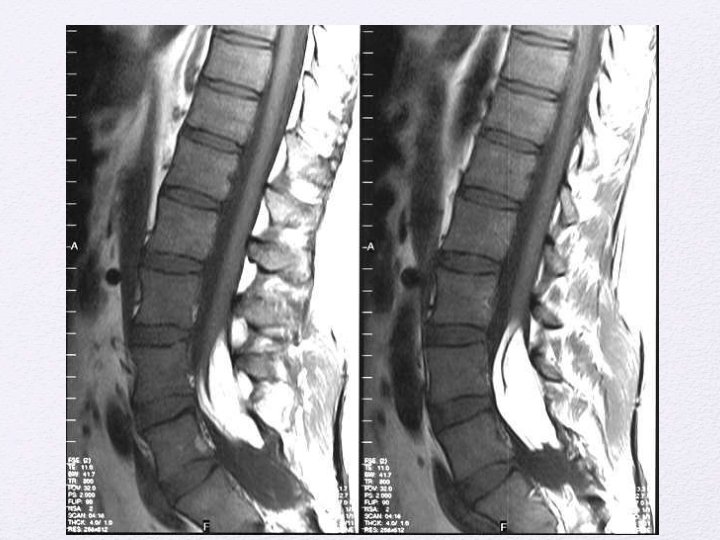

Lipoma of the terminal filum Less severe form of Occult SD More than 2 mm thickness of the filum on MR imaging Frequently assosciated with sacral/gluteal cleft dimples. May be associated with VATER association, imperforate anus, cloacal extrophy and other urogenital abnormalities. Sometimes a/w sacral agenesis Reflects defective secondary neurulation

Orthopedic Clinical presentation Urologic Pain • All asymptomatic infants and symptomatic adults are surgical candidates. • Surgical procedure is the exposure of filum through lumbosacral laminectomy or interlaminar approach The filum identified separated from nerve roots and cut.